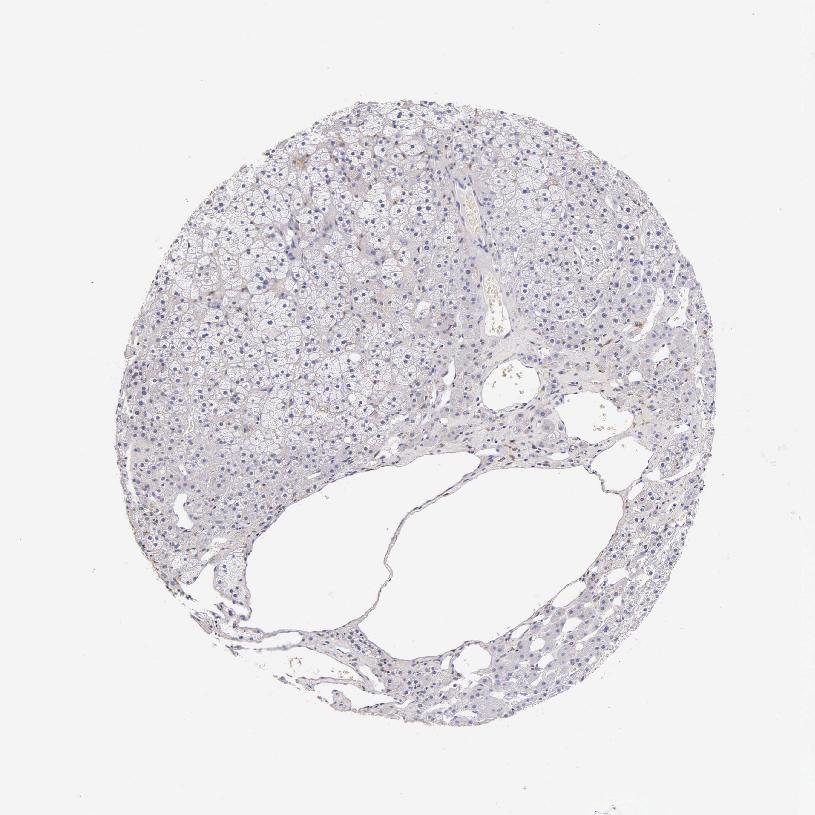

ADRENAL GLAND - Antibody stainingi

Antibody staining in the annotated cell types in the current human tissue is reported as not detected, low, medium, or high, based on conventional immunohistochemistry profiling in selected tissues. This score is based on the combination of the staining intensity and fraction of stained cells.

Each image is clickable and will lead to virtual microscopy that enables deeper exploration of all samples and also displays staining intensity scores, fraction scores and subcellular localization as well as patient and tissue information for each sample.

Antibody HPA018156Antibody HPA048998Antibody CAB000457

Glandular cells MediumMediumNot detected